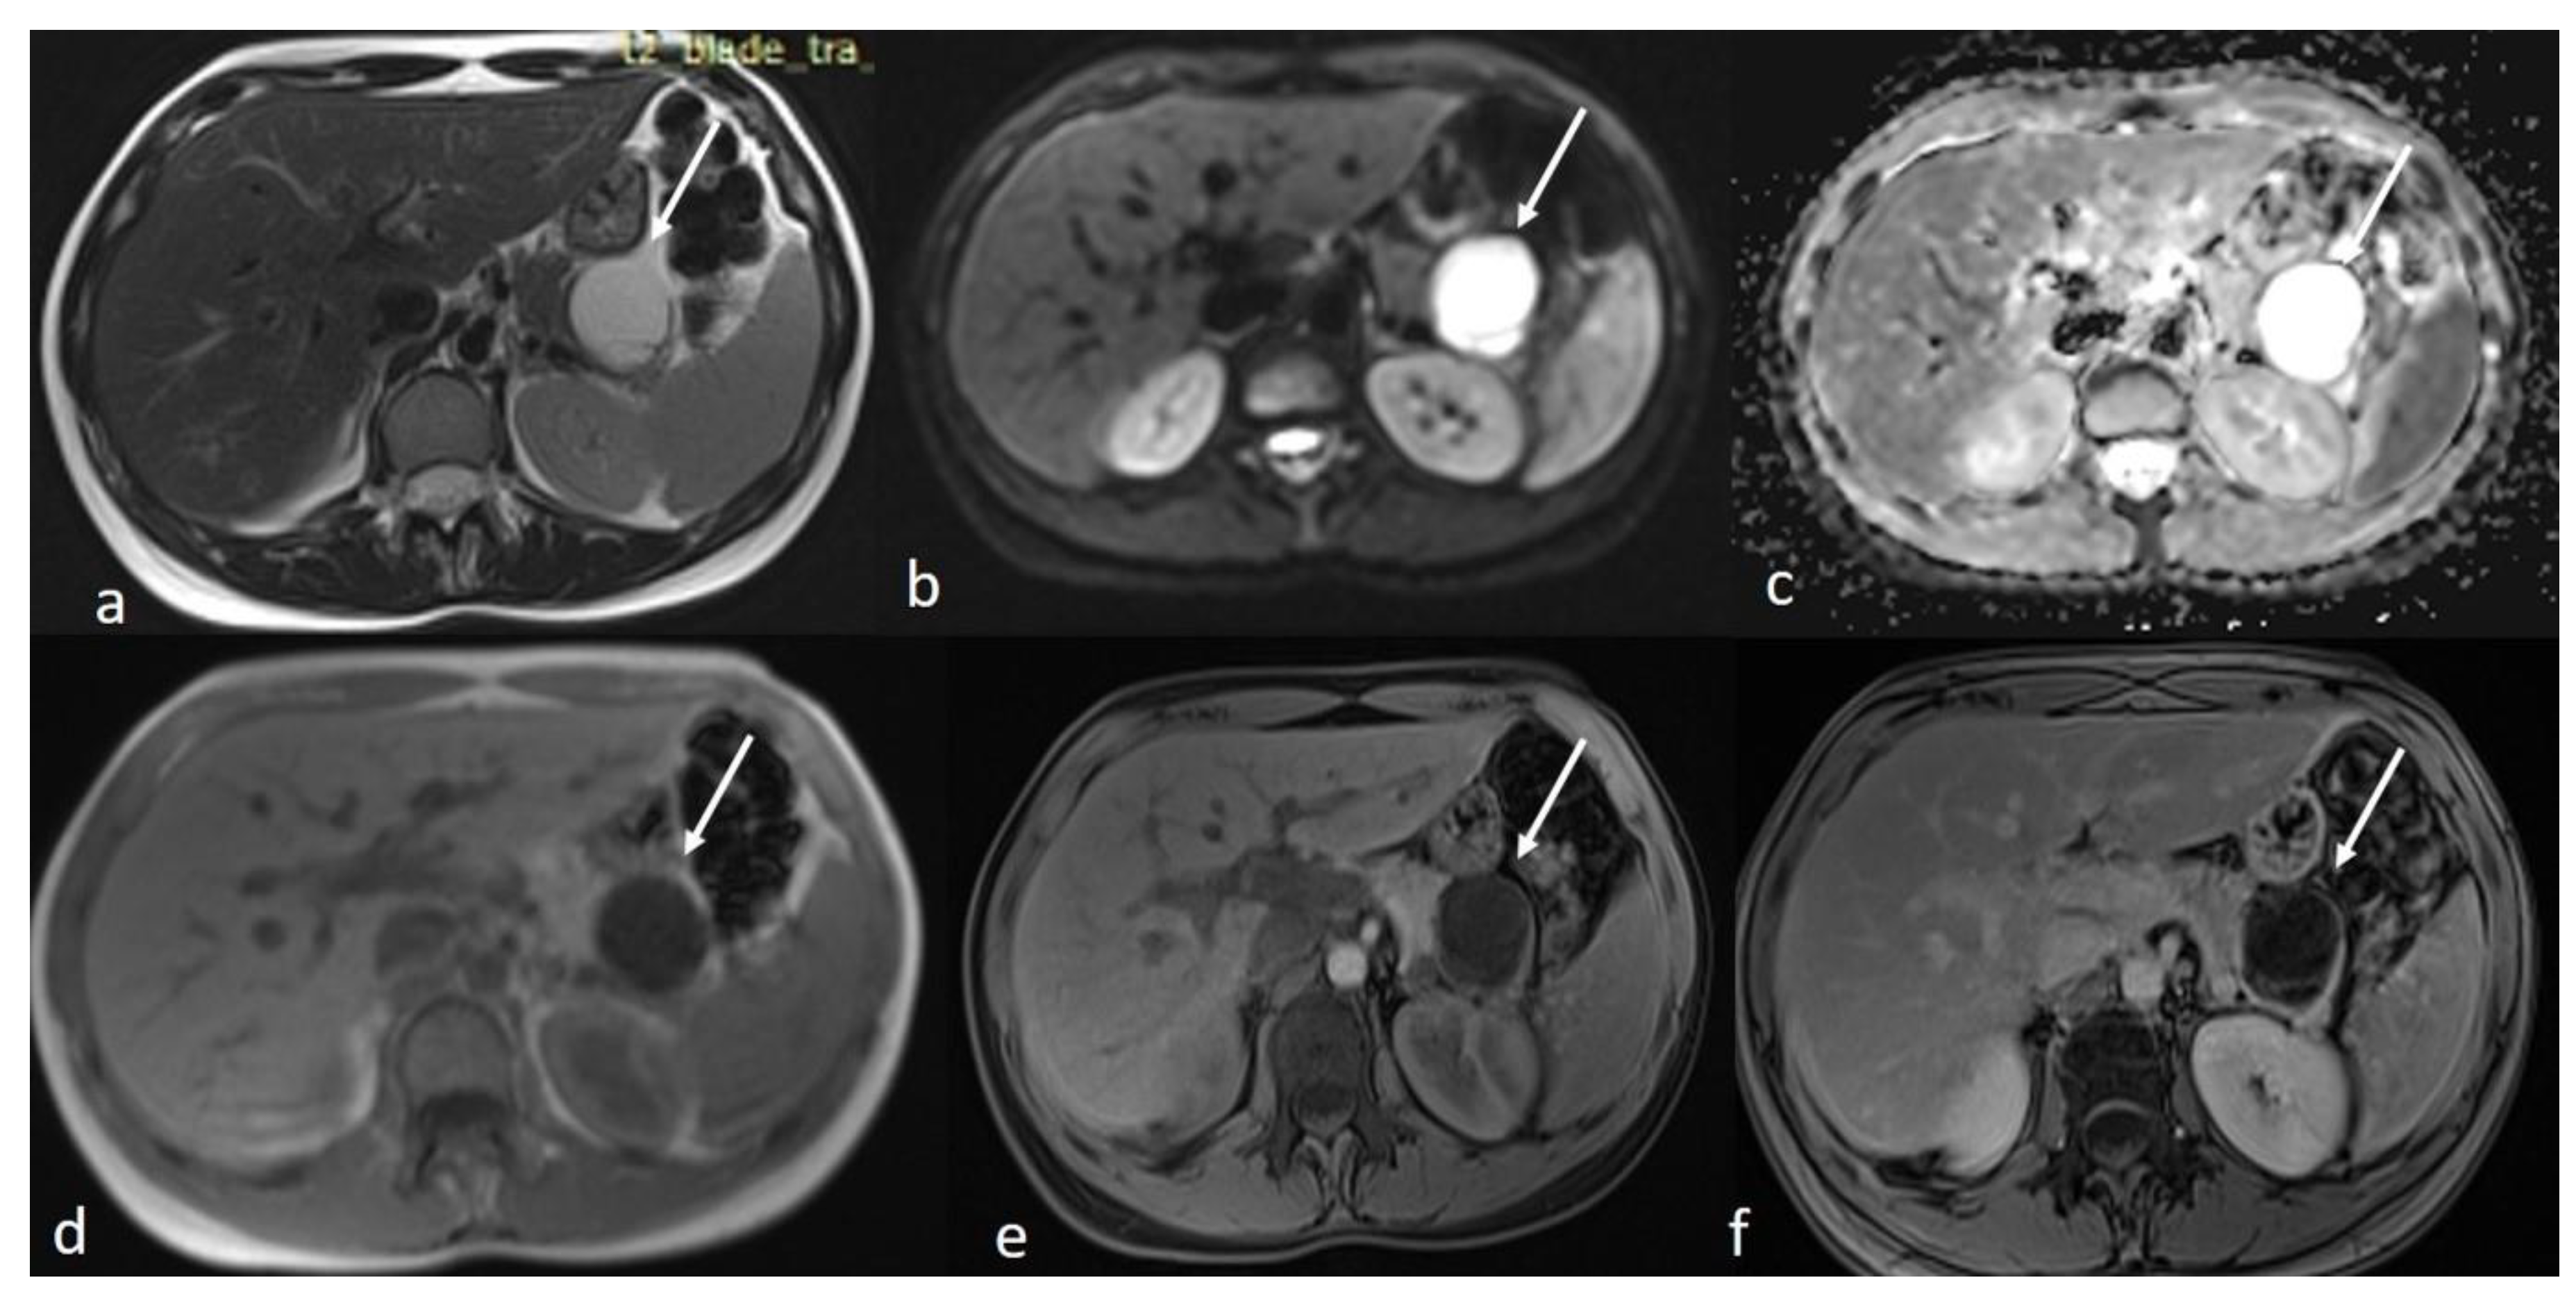

An MRI of the abdomen, performed approximately one year prior to admission, revealed a cystic thin-walled formation with internal septa, located in the dorsal part of the tail of the pancreas. The lesion measured approximately 3.9 cm in diameter and exerted pressure between the pancreas and the greater curvature of the stomach. The walls and internal diaphragms of the cyst showed enhancement post-contrast injection. There was no evidence of pancreatic duct dilation. Differential diagnoses at this stage included pancreatic cystic lesions such as cystadenoma, though the patient’s age was considered atypical, as well as other lesions like cystic lymphangioma or replication cysts. Additionally, incidental findings of mild hepatomegaly and a 9.5 mm hemangioma in the eighth hepatic segment were noted, along with small lymph nodes (Figure 2). In the absence of high-risk features or significant symptoms, a watch-and-wait approach with periodic monitoring was deemed appropriate.

Figure 2.

First MRI axial sequences of the upper abdomen. (a) T2 Blade axial sequence showing hyperintensity of the cyst (white arrows). (b,c) DWI and ADC showing no internal restriction of the cystic lesion. (d) T1 Vibe showing a hypointense cystic lesion at the tail of the pancreas. (e,f) T1 Vibe post-contrast at arterial and venous phases showing only minimal enhancement of the cyst wall and the septations with no internal solid component.